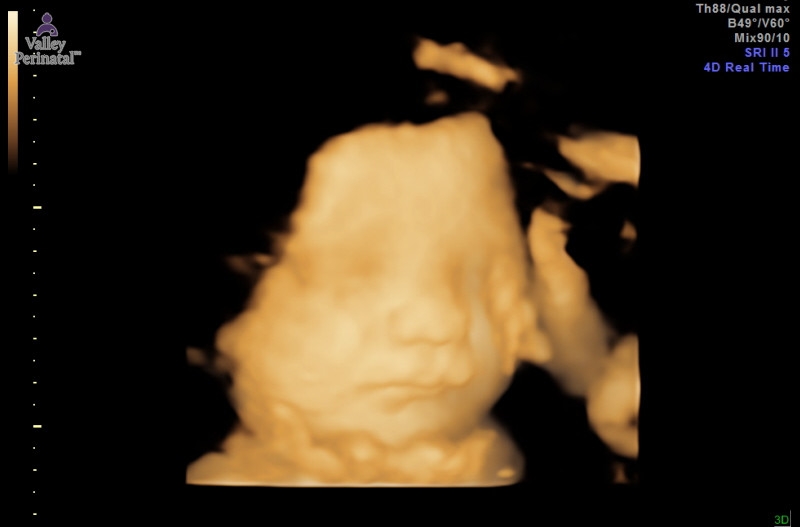

Got to see this precious face yesterday in our 32 week size check ultrasound. He's measuring about a week ahead and weighing just over 4 pounds which makes me feel like he's going to be a little chubby. Its always such a relief to see that everything still looks good.